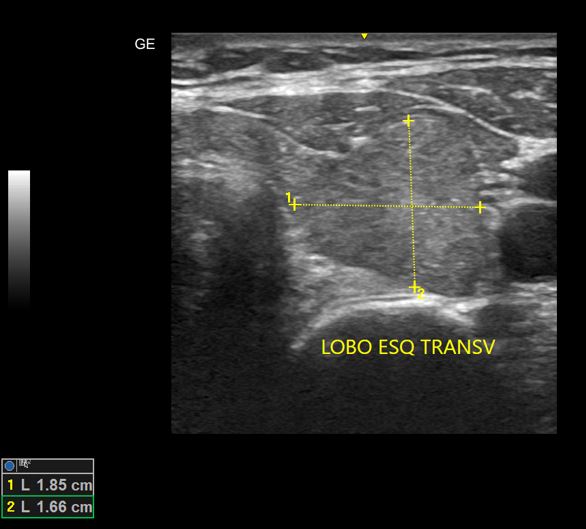

Tireoidite de Hashimoto

USG de Tireoide